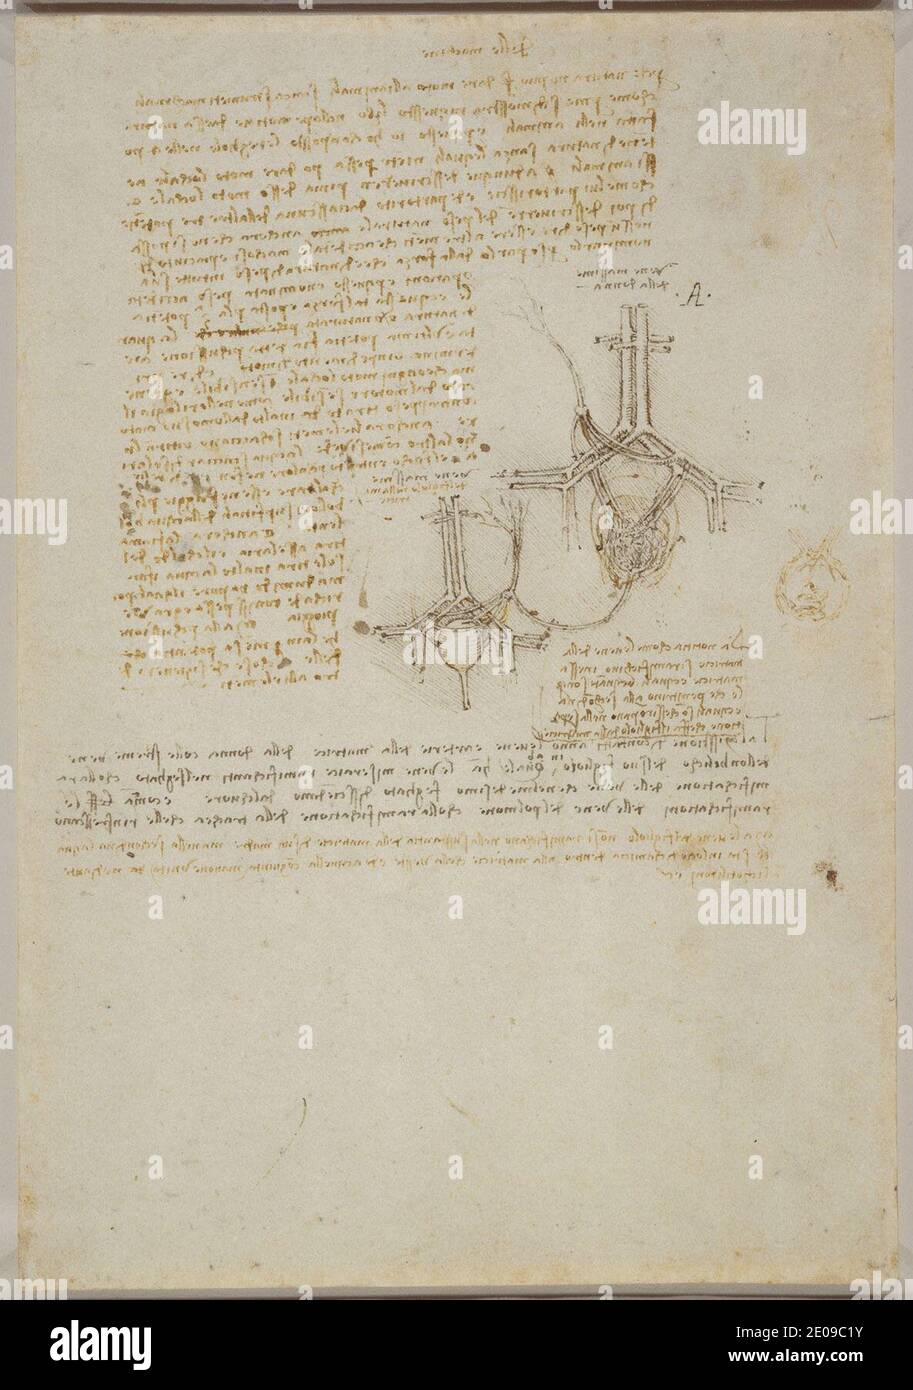

RM2E09C1Y–Leonardo da Vinci - Studien über die Blutversorgung der Gebärmutter und des Fötus, und Notizen über die Mechanik c.1510-13.